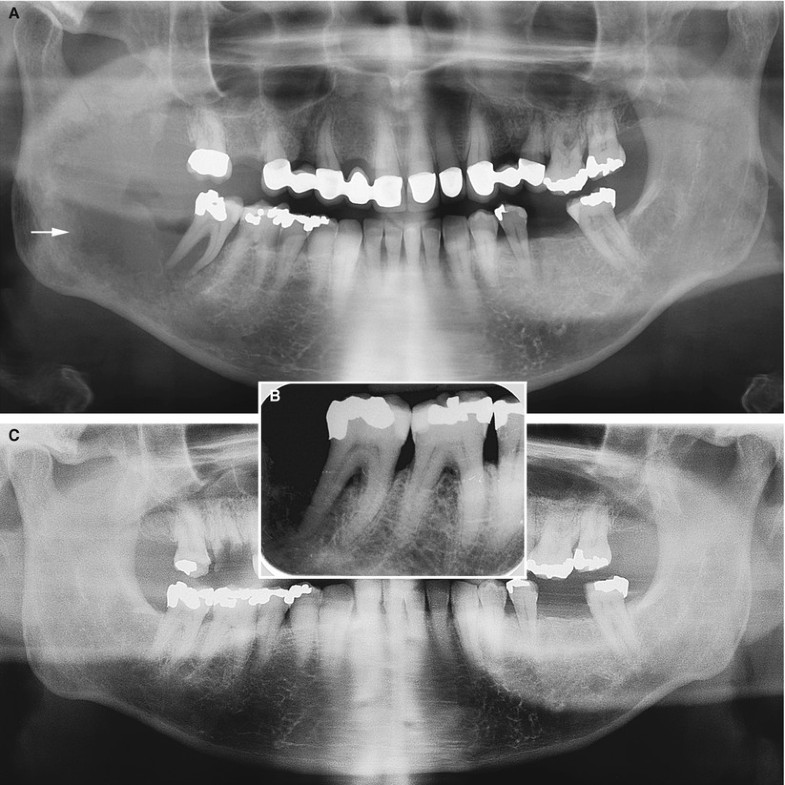

(A) The radiographic appearance of the lesion on the jawbone is Malignant Tumor Jaw Bone A person with jaw bone cancer develops a malignant tumor on their mandible, lower jaw bone, or maxilla, which is the hard palate or upper jaw bone. Jaw tumors and cysts — sometimes referred to as odontogenic or nonodontogenic, depending on their origin —. Rarely, cancerous (malignant) tumors form within your jawbone or from the tissue that’s involved in forming. Malignant Tumor Jaw Bone.